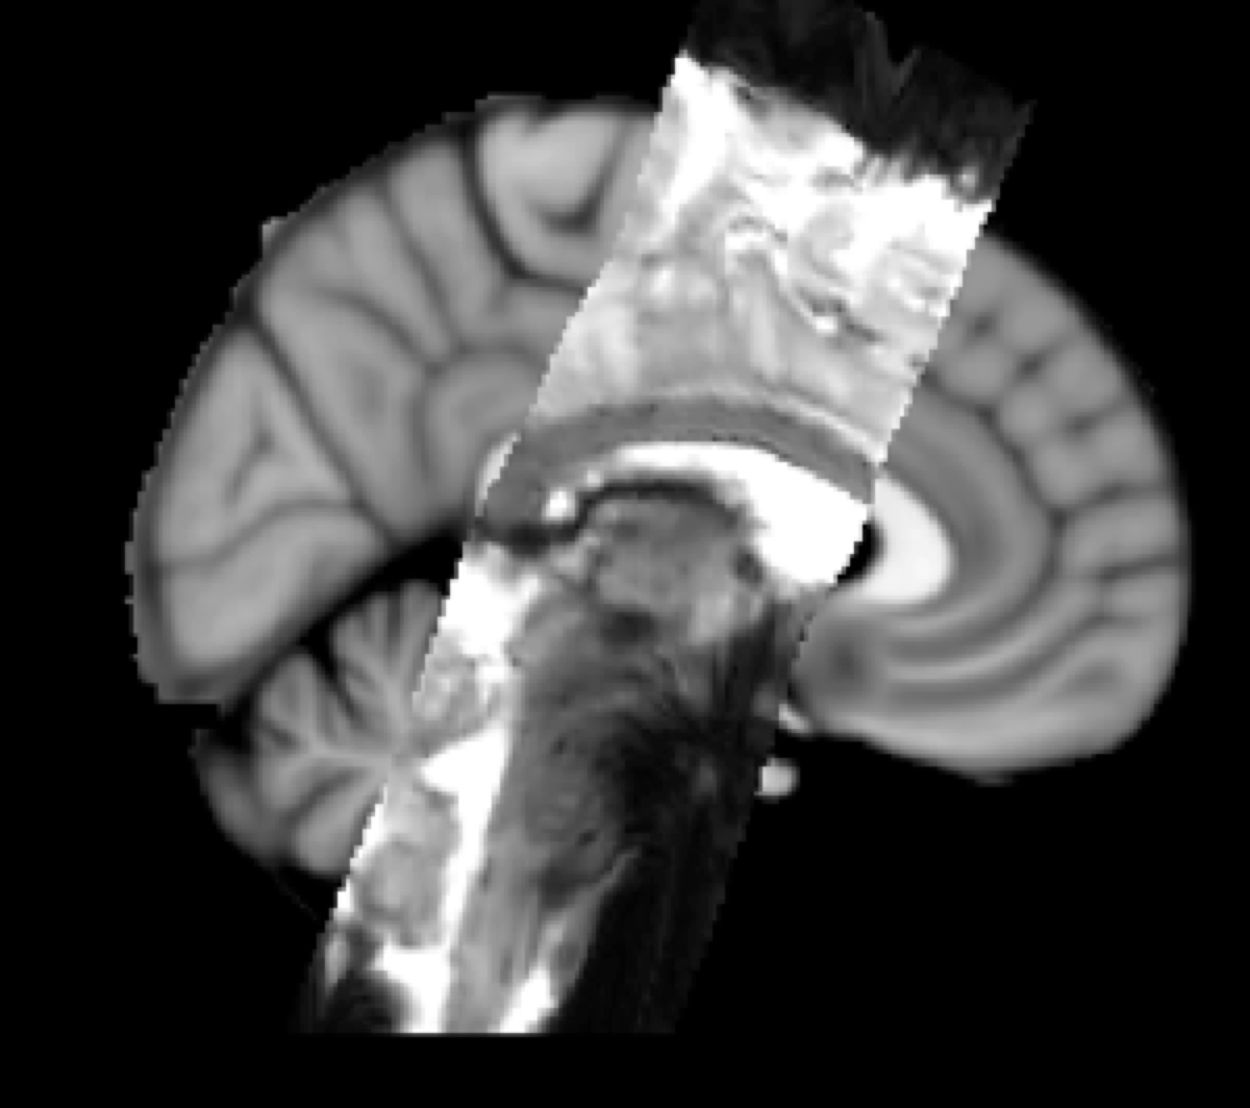

Example result: EPI (functional) resampled to standard space

FMRI to Standard Space Example